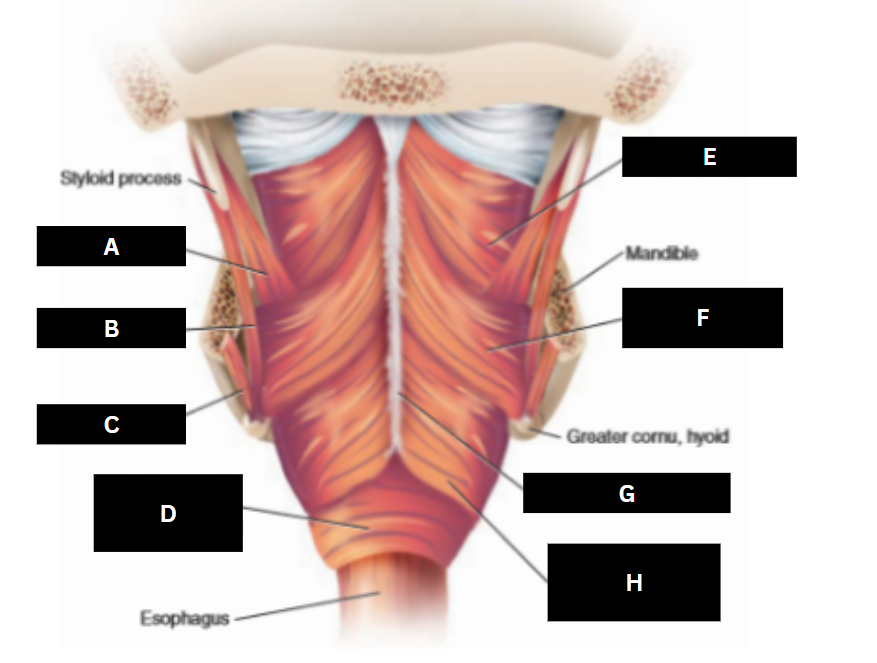

Stylopharyngeus

A

Styloglossus

B

Stylohyoid

C

Cricopharyngeus

D

Superior pharyngeal constrictor

E

Middle pharyngeal constrictor

F

Pharyngeal raphe

G

Inferior pharyngeal constrictor

H